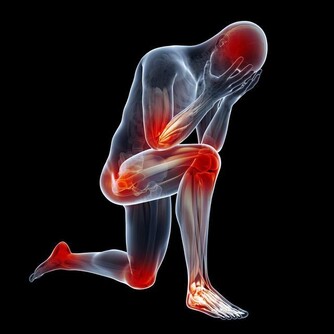

如果癌症擴散到前列腺外,會出現其他症狀。這些症狀包括:

1. 勃起困難;

2. 感覺很累,怎麼著都不舒服;

3. 骨頭或背部感覺疼痛;

4. 出現不明原因的體重減輕。